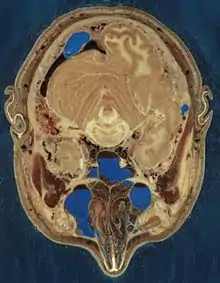

The Visible Human Project is an effort to create a detailed data set of cross-sectional photographs of the human body, in order to facilitate anatomy visualization applications. It is used as a tool for the progression of medical findings, in which these findings link anatomy to its audiences.[1] A male and a female cadaver were cut into thin slices which were then photographed and digitized. The project is run by the U.S. National Library of Medicine (NLM) under the direction of Michael J. Ackerman. Planning began in 1986;[2] the data set of the male was completed in November 1994 and the one of the female in November 1995. The project can be viewed today at the U.S. National Library of Medicine[3] in Bethesda, MD. There are currently efforts to repeat this project with higher resolution images but only with parts of the body instead of a cadaver.

The male cadaver was encased and frozen in a gelatin and water mixture in order to stabilize the specimen for cutting. The specimen was then “cut” in the axial plane at 1 millimeter intervals. Each of the resulting 1,871 “slices” was photographed in both analog and digital, yielding 15 gigabytes of data. In 2000, the photos were rescanned at a higher resolution, yielding more than 65 gigabytes. The female cadaver was cut into slices at .33 millimeter intervals, resulting in some 40 gigabytes of data.

The data are supplemented by axial sections of the whole body obtained by computed tomography, axial sections of the head and neck obtained by magnetic resonance imaging, and coronal sections of the rest of the body also obtained by magnetic resonance imaging.